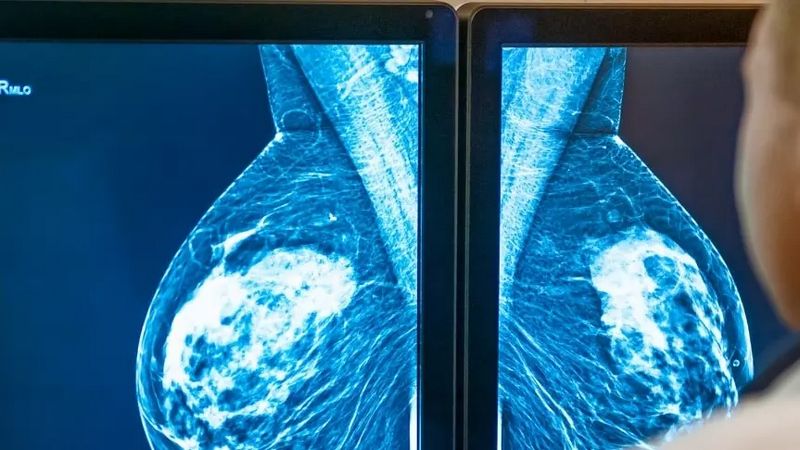

I Lea prevedono screening gratuiti per: Mammografia (donne 50-69 anni), Tumore della cervice uterina (donne 25-64 anni), Tumore colon-rettale (uomini e donne 50-69 anni).

La Calabria si posiziona al 21° e ultimo posto in tutte e tre le classifiche del report della Fondazione Gimbe. Per quanto riguarda lo screening mammografico, l’estensione (percentuale della popolazione target che riceve un invito) è del 49,4% (media Italia 93,6%), e l’adesione è dell’8,1% (media Italia 49,3%). Secondo la Fondazione Gimbe, la bassa adesione è legata a problemi organizzativi nella gestione degli inviti, comuni anche ad altre regioni del Mezzogiorno (Molise escluso).